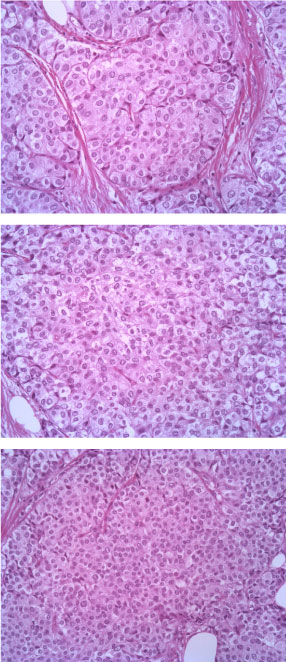

The tumor consists of densely cellular, solid nests (prevalent aspect in our case) and trabeculae of round cells of small-medium size, with abundant clear cytoplasm, separated by delicate fibrovascular stroma. The cells have round, regular nuclei and show some palizading arrangement at the periphery of the nests.

The immunophenotype was coherent with the diagnosis, showing bright positivity for synaptophysin, while CK5 and CK7 were negative.

Estrogenic and progestinic receptors showed diffuse positivity as well, with low proliferative fraction (Ki67/Mib1 < 5%) and no amplification of HER2 gene (data not shown) (Figure 1, Figure 2, Figure 3, Figure 4, Figure 5, Figure 6, Figure 7, Figure 8, Figure 9 and Figure 10).

Figure 3: EE 20X. View Figure 3

Figure 4: Synaptophisyn 10X. View Figure 4

Figure 5: CK7 10X. View Figure 5